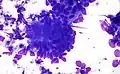

Colorectal adenocarcinoma. Field stain.

Colorectal adenocarcinoma. Field stain. Granuloma. Field stain.